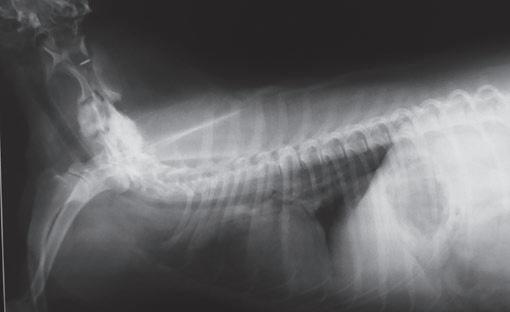

Issuu converts static files into: digital portfolios, online yearbooks, online catalogs, digital photo albums and more. Sign up and create your flipbook.